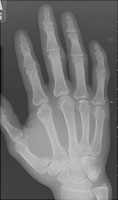

The Bennett fracture is an intraarticular fracture of the base of the first metacarpal. The fracture must involve the first carpometacarpal joint to be called a Bennett fracture. The action of the abductor pollicis longus causes distraction of the fracture fragments. The volar base of the first metacarpal stays with the trapezium.

- Click on the image for a larger versionAOblique radiograph of the hand. There is an intraarticular fracture at the base of the first metacarpal.